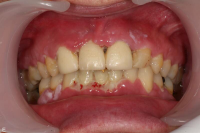

Karakteriseras av approximala nekrotiska och fibrintäckta sår (nedsmälta papiller) som är smärtsamma vid beröring och mycket lättblödande.

Patienten kan ha påverkat allmän tillstånd och ofta foeter ex ore.

I anamnesen förekommer ofta kombination av nedsatt immunförsvar, rökning, stress och dålig munhygien. HIV/Aids kan finnas som bakgrundsfaktor.

Nekrotiserande ulcerös gingivit: